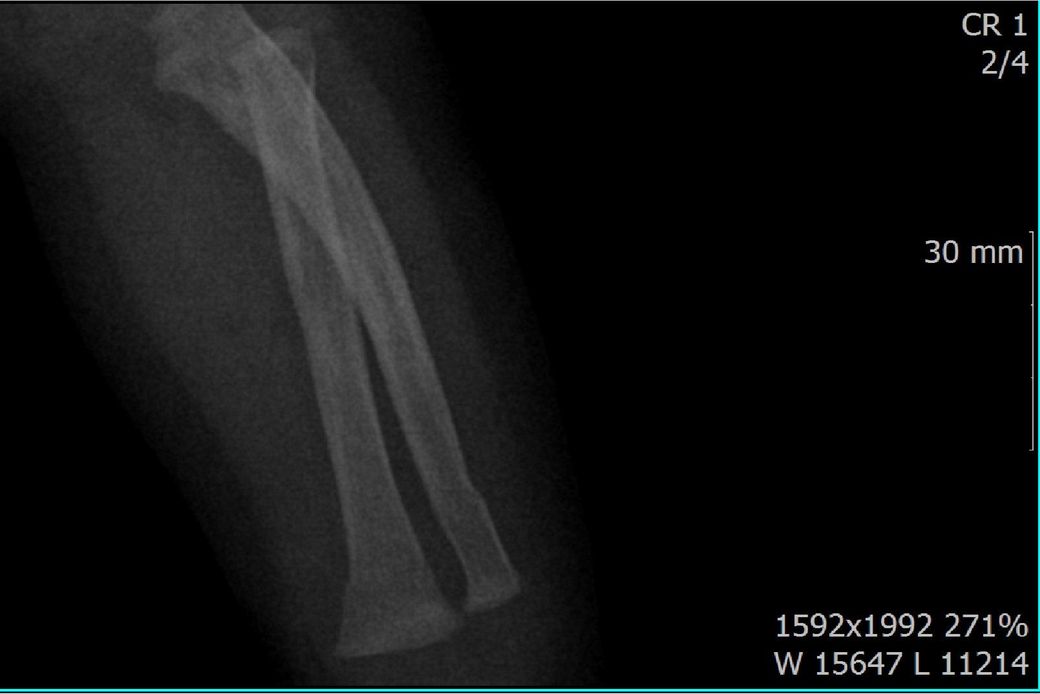

다름이 아니라, 첨부드린 엑스레이(X-ray) 사진처럼 골절 사실을 알게 되고 골절 발생 시점 대략적으로나마 추정시기를 파악하려고 문의 드리게 되었습니다

1) 3월 30일 촬영한 X-ray만으로 정확한 골절 시기를 100% 특정하는 데에는 한계가 있다는 점 충분히 인지하고 있기에 촬영날짜 기준으로 대략적으로 어느정도 시점에서 발생되었을 것으로 추측(ex 당일, 7~10일전, 7~14일 전, 10일 ~ 20일전, 14일 ~ 30일전 등등등)되는지 이해하고 싶습니다.

• 3번 째 사진